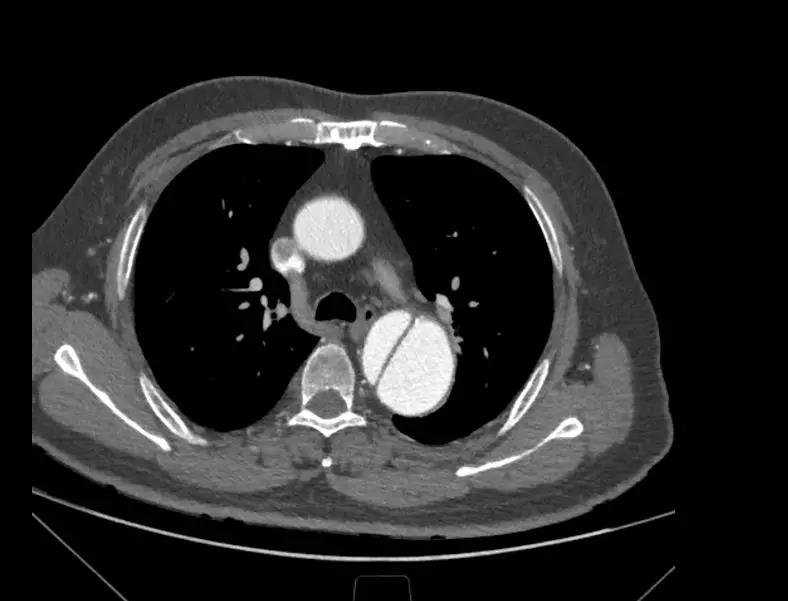

6月25日,中国医学科学院阜外医院向大会现场直播了一台采用彩神在线网信彩票-彩神通免费版下载-彩神8争霸vlll-彩神购彩购彩大厅-彩神软件陆立根免费版-彩神ll争霸3-彩神ll彩神8-彩神ll争霸彩票-拼搏在线彩神网网页版新型主动脉支架系统进行的手术。手术由舒畅教授担任主要术者,接受手术的患者为一名65岁男性,入院后经CTA检查确诊为“慢性B型主动脉夹层”,夹层破口紧邻左锁骨下动脉,病变累及到两侧髂总动脉,主动脉真腔严重受压,假腔巨大,近端锚定区严重不足,病情十分危重。

术中通过DSA造影显示:主动脉夹层破口位于左锁骨下动脉近端,真腔压闭。舒畅教授通过左锁骨下动脉预置Longuette™裙边支架,释放 Ankura™ Pro主动脉主体覆膜支架,封堵破口后通过裙边支架显影点准确定位,释放裙边支架,凭借着舒畅教授精湛的手术操作和器械的优异性能,手术过程非常顺利,胸主动脉支架释放良好,患者的主动脉夹层破口封闭良好,左锁骨下动脉释放的裙边支架血流通畅,没有内漏发生。由于患者远端真腔较小,为了保证远端的血流,植入了一个cuff支架,造影显示远端真腔打开良好。

(图:术前造影)